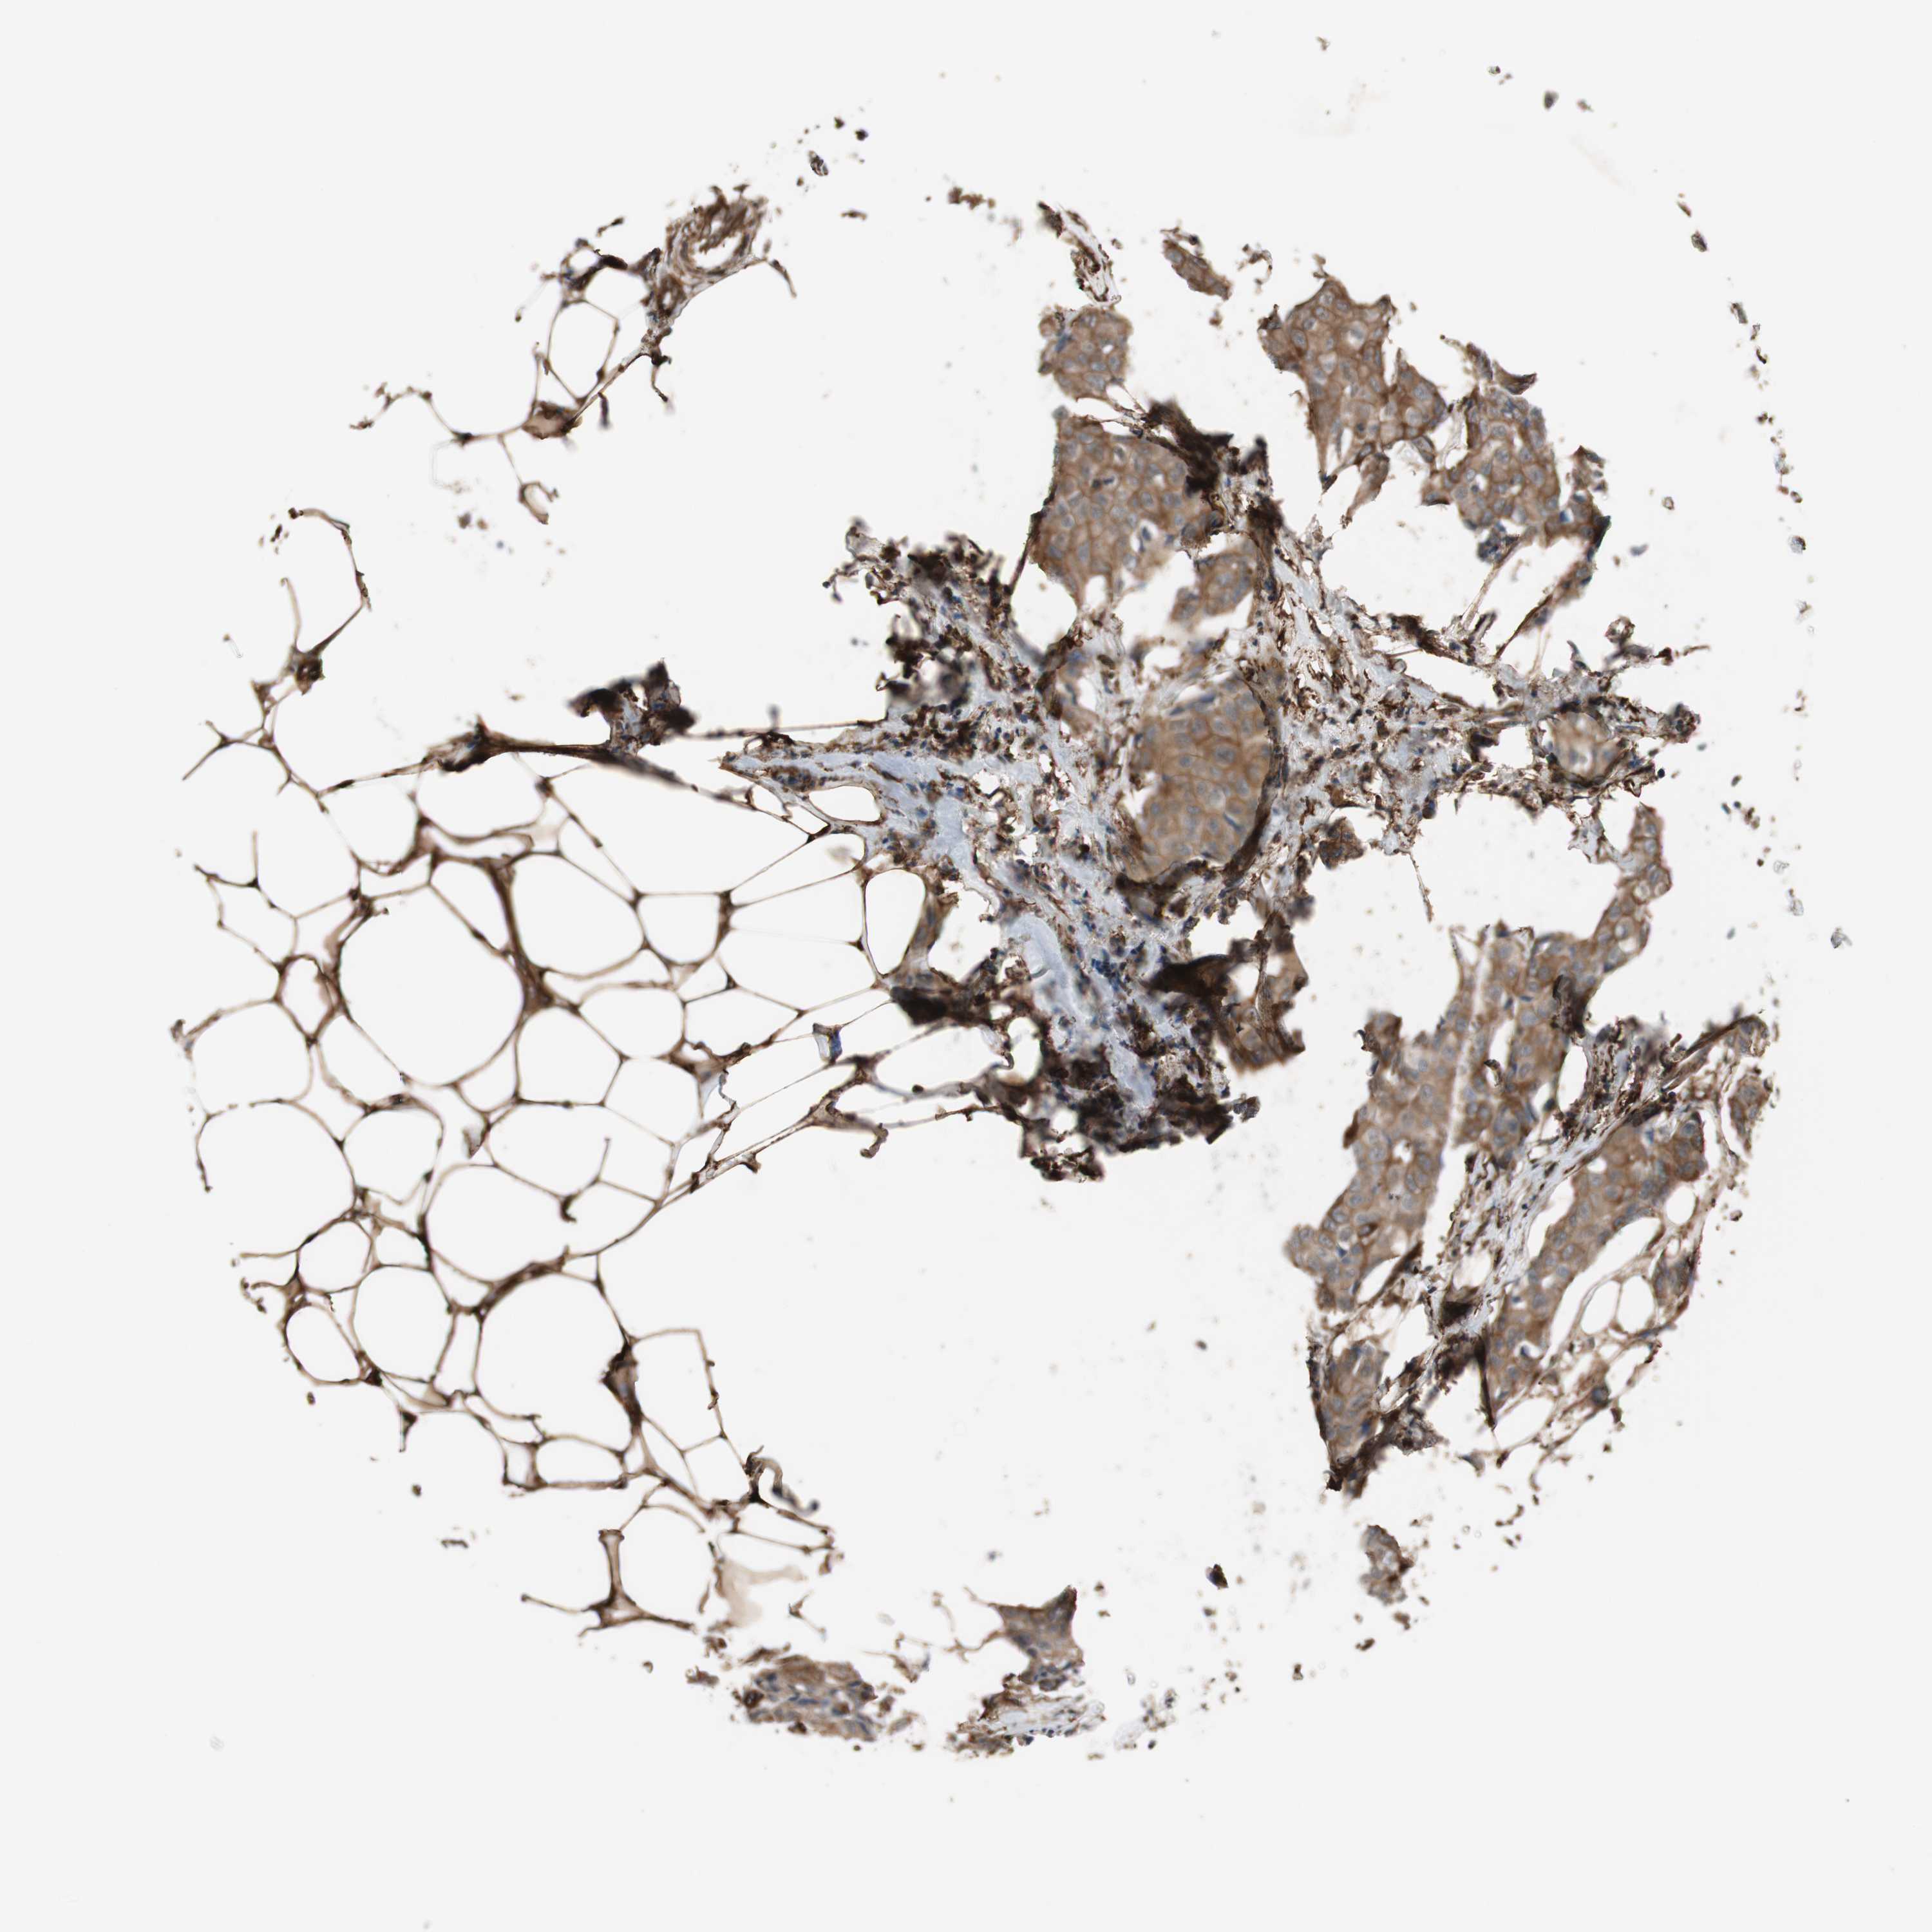

BRCA TCGA BRCA VALIDATION PROTEIN EXPRESSION